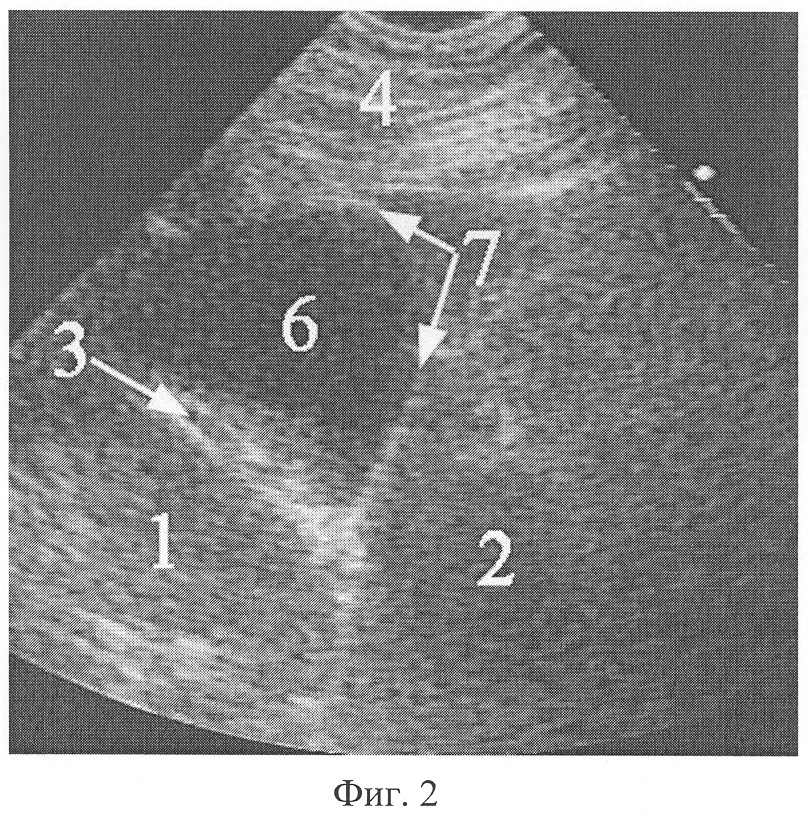

Фиг.1. Эхограмма абдоминомедиастинальной липомы при поперечном ультразвуковом сканировании справа парастернально из межреберья над местом прикрепления реберной дуги к грудине.

На фиг.1 обозначено: 1 – печень, 2 – сердце (лоцируется нечетко при движении), 3 – медиальная поверхность правого купола диафрагмы, 4 – мягкие ткани грудной стенки, 5 – абдоминомедиастинальная липома.